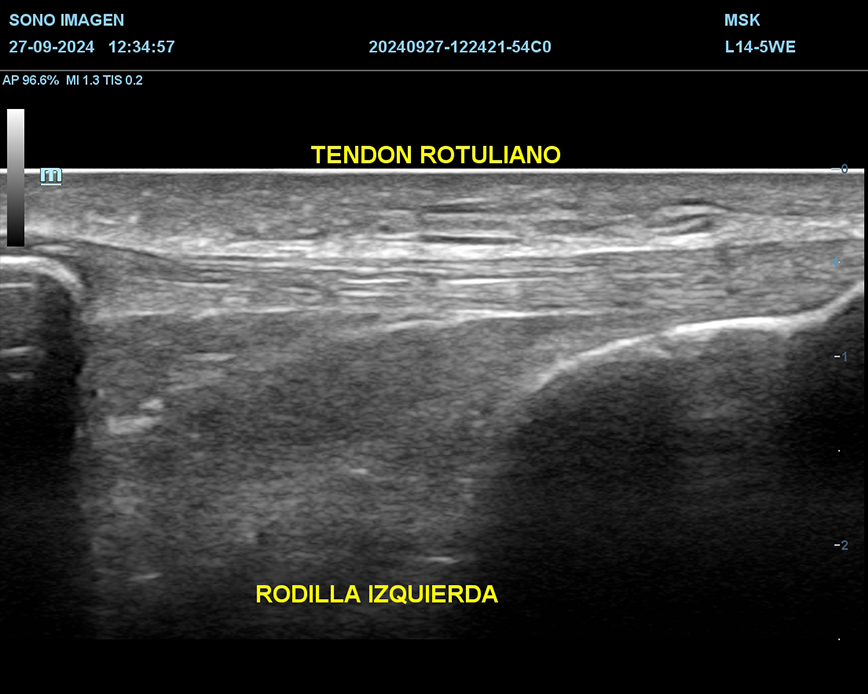

Ecografía de rodilla

- evaluación del dolor de rodilla

- lesiones de tejidos blandos: tendinosis, desgarros ligamentosos, rupturas meniscales.

- derrame articular

- inflamación o infección

- evaluación de lesiones deportivas

- quiste de Baker

- seguimiento postoperatorio

- traumatismos